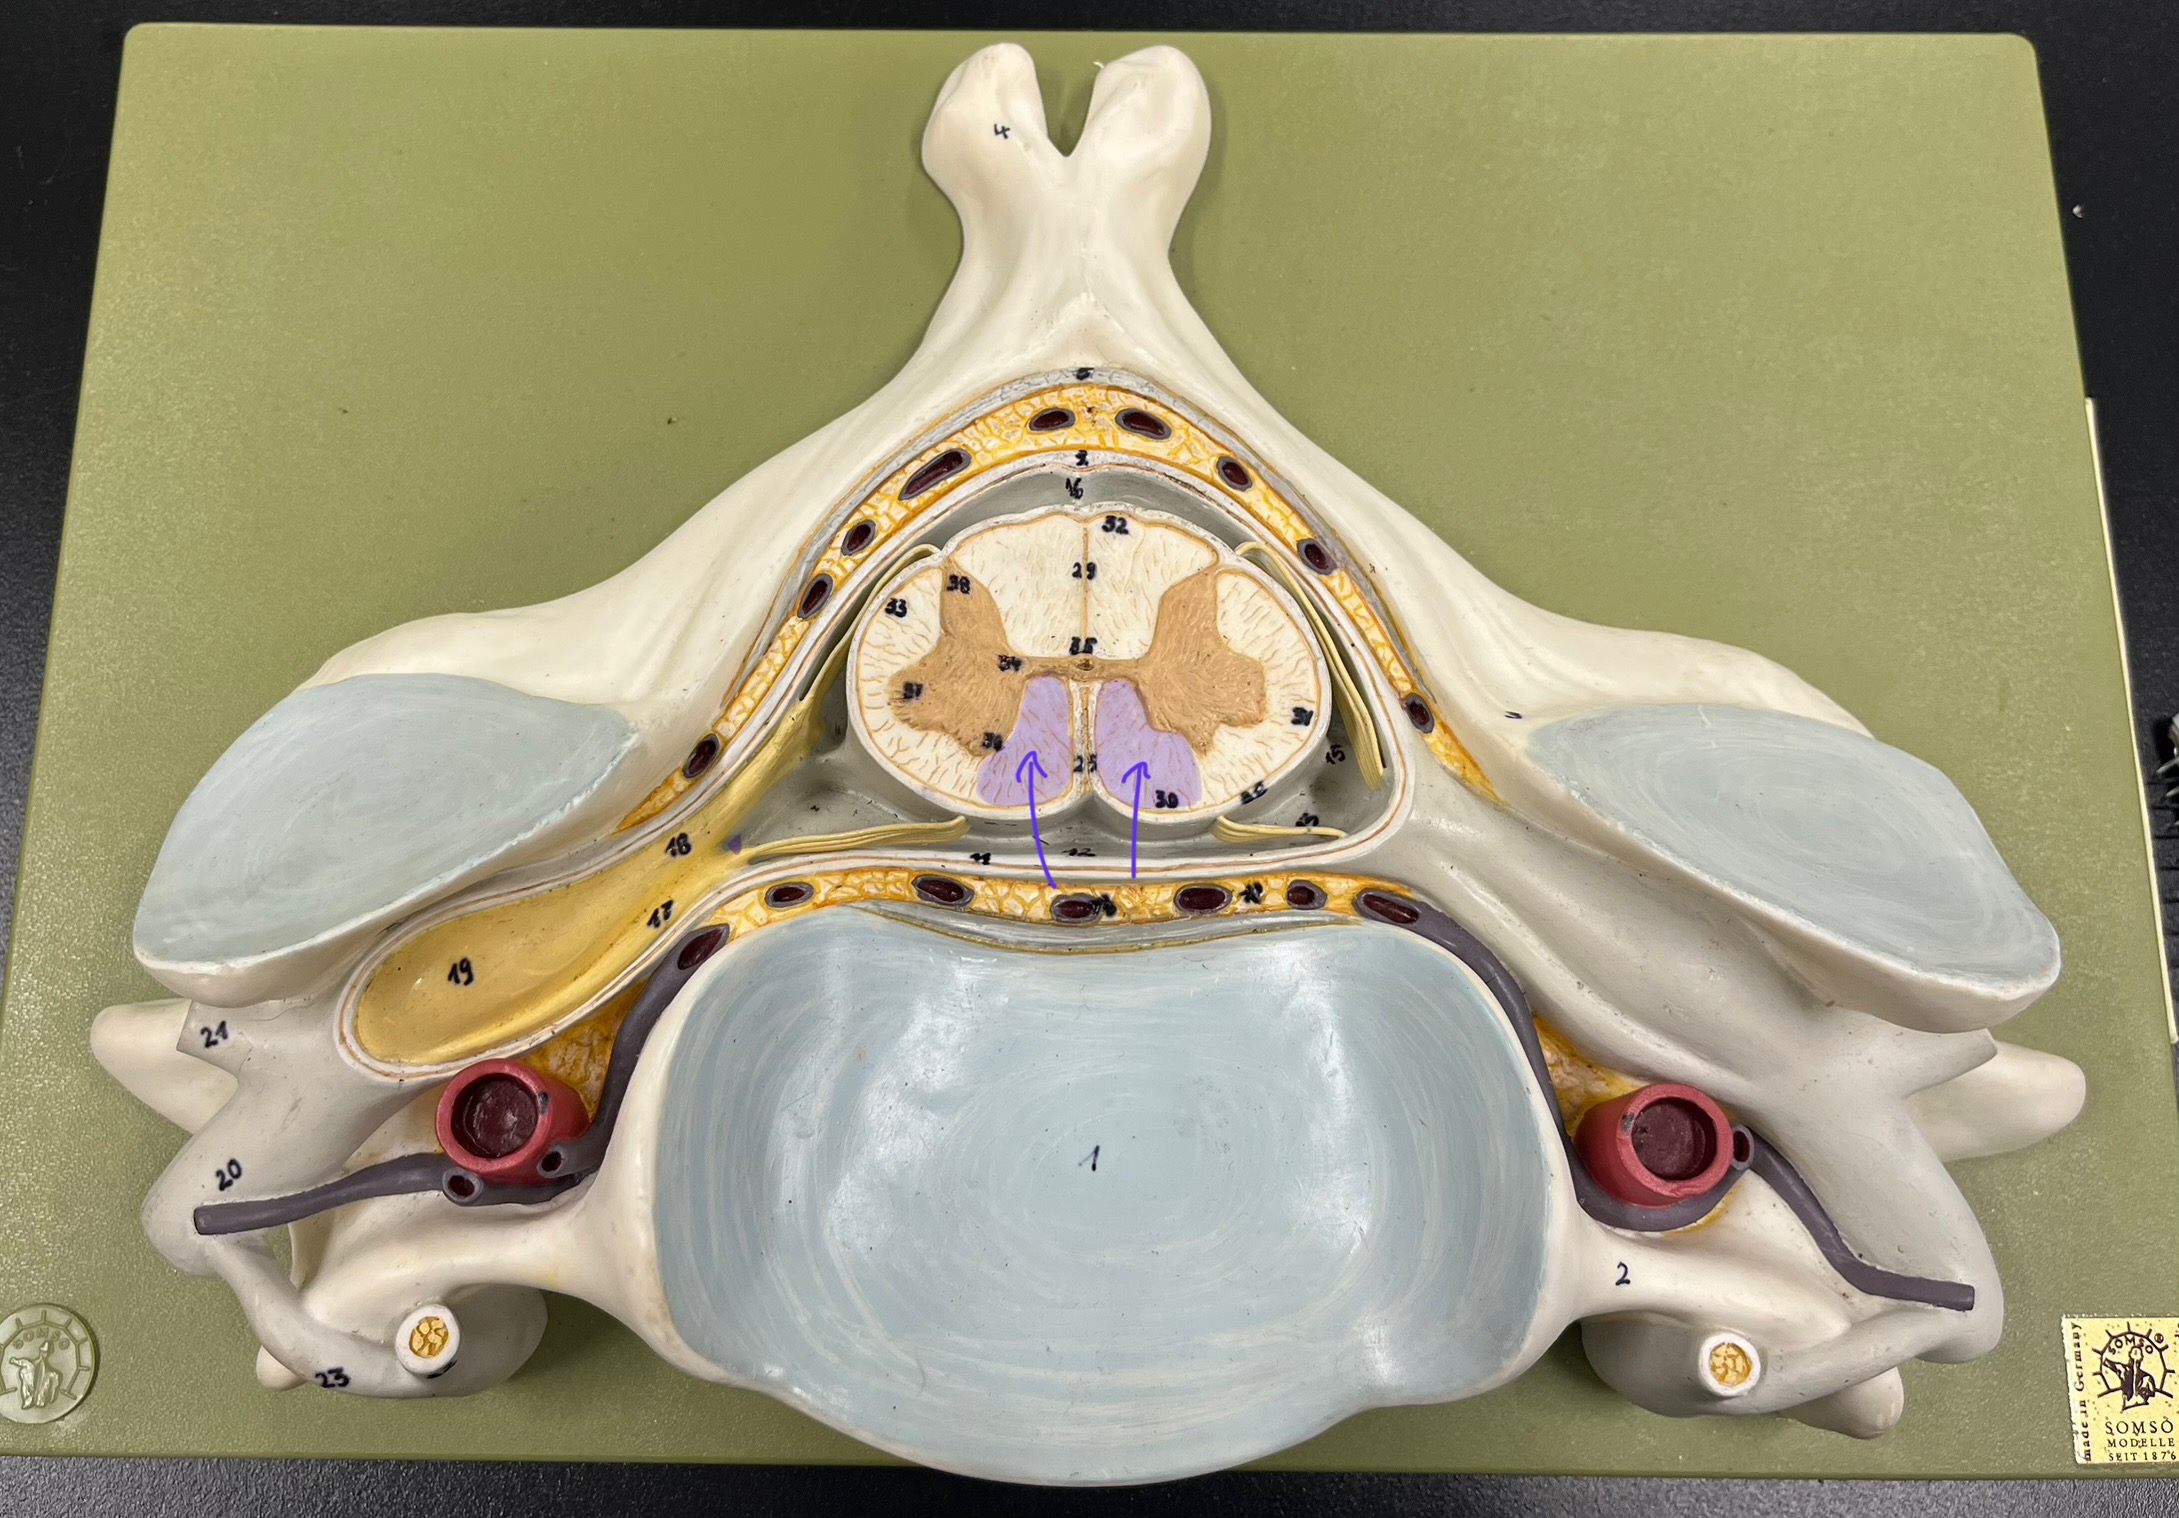

posterior (dorsal) horn

posterior (dorsal) horn; R—>L

anterior (ventral) horn

lateral horn (selected models)

gray commissure

central canal

anterior column

lateral column

posterior column

white commissure